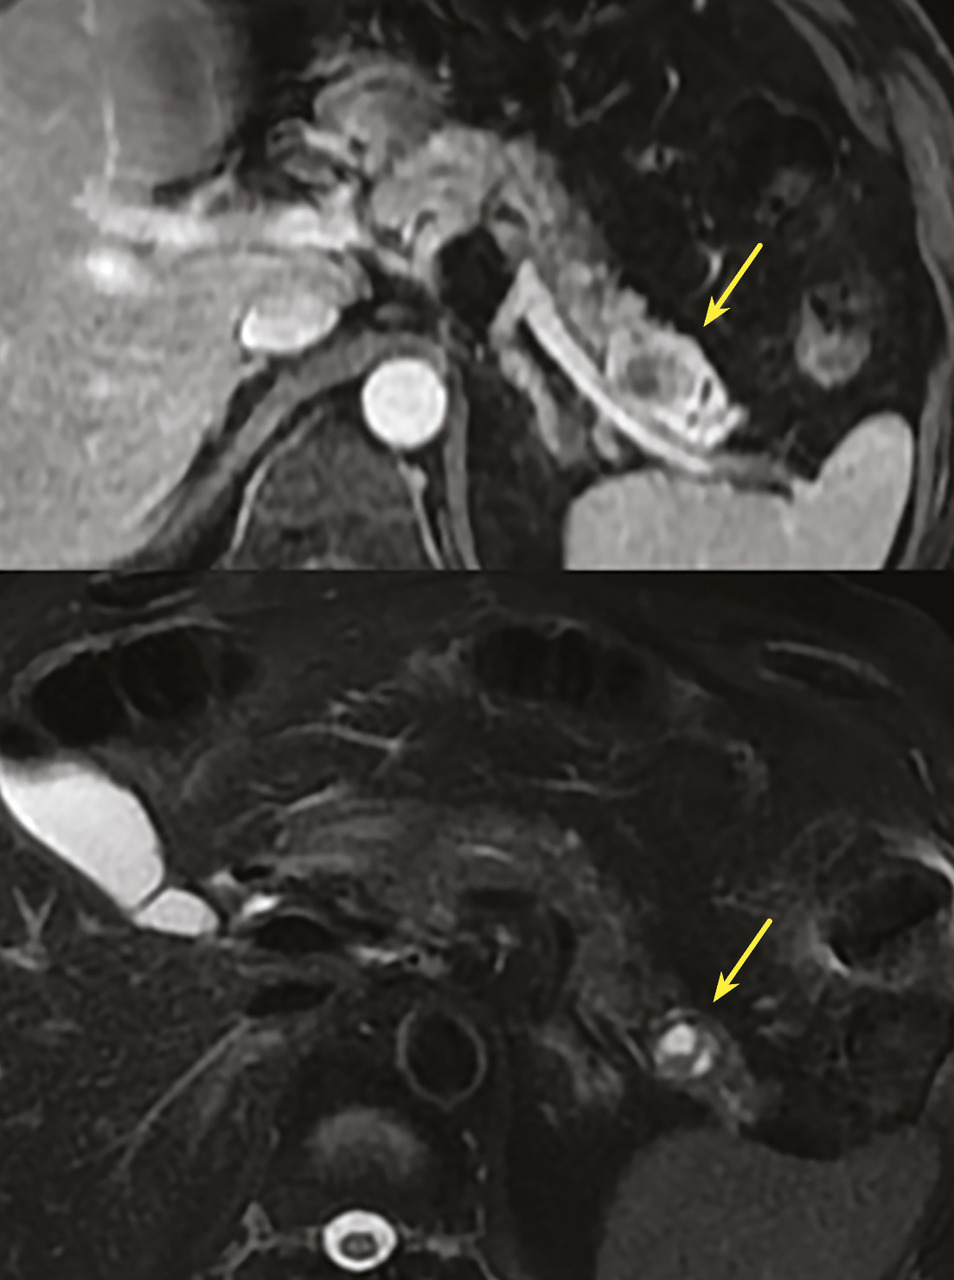

Les TIPMP sont des lésions canalaires intra-épithéliales développées aux dépens des canaux pancréatiques (principal ou/et secondaires) [fig. 1]. Elles prédominent au niveau de la tête et du crochet, mais peuvent concerner toute la glande. La composante kystique des TIPMP présente un épithélium de type mucineux avec production de mucus. Au cours du processus d’oncogenèse, des papilles commencent à se former, et différents phénotypes cellulaires distincts ont été décrits, corrélés à leur pronostic.

Toujours parmi les LKP rares à potentiel malin, on compte les tumeurs neuro-endocrines (TNE) kystiques (20 % des TNE pancréatiques) [fig. 5]. De découverte fortuite et non fonctionnelles, les TNE kystiques sont uniques, uniloculaires, bien différenciées, de bas grade, c’est-à-dire avec un indicateur de prolifération Ki67 < 3 %, et la présence d’une masse hypervasculaire (nodule) au niveau de la paroi. La partie charnue tissulaire peut être de petite taille.